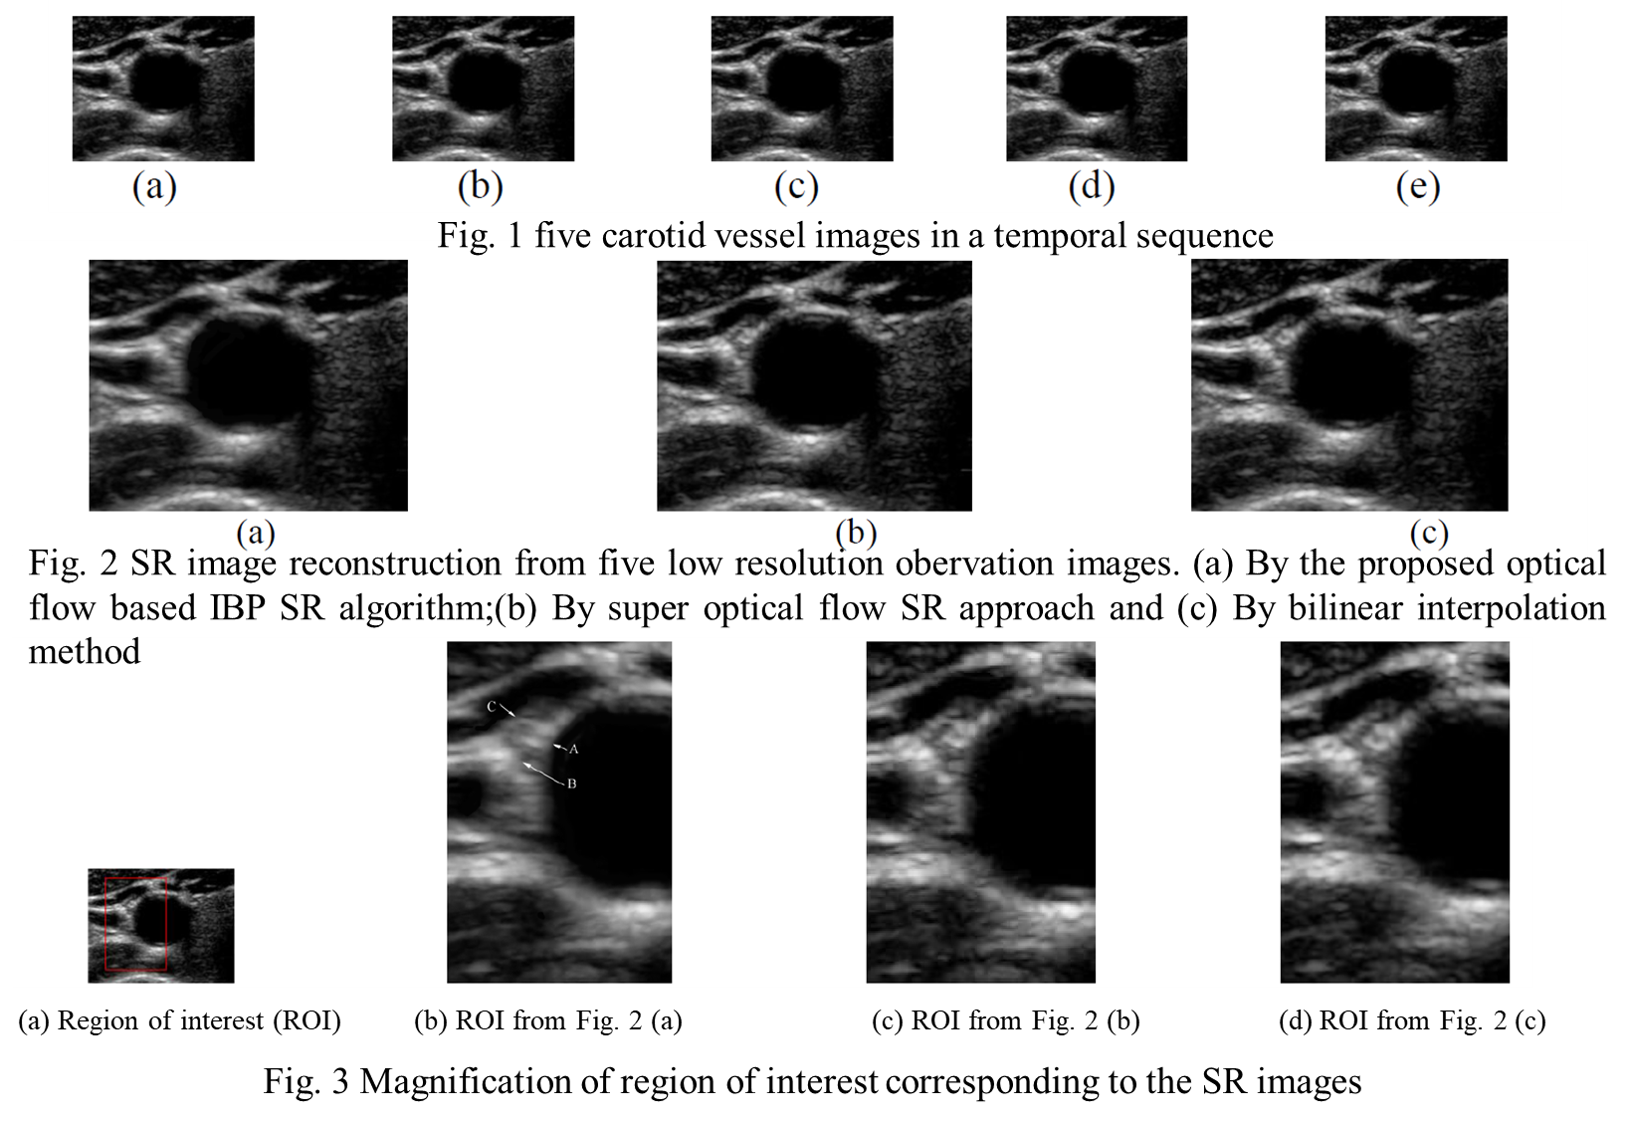

- HongMei Zhang, MingXi Wan, JinJin Wan,XuLei Qin. Super-Resolution Reconstruction of Deformable Tissue from Temporal Sequence of Ultrasound Images, 2010 International conference on artificial Intelligence and Computational Intelligence. Vol. 1, pp.337-342.

总经费:63 万元人民币(3) 项目名称:“超分辨超声血管应变估计和弹性成像方法和实验研究”

项目负责人:张红梅

资助来源:国家自然科学基金(项目编号 60801057)

研究时间:2009 年 1 月 1 日 - 2011 年 12 月 31 日

总经费:20 万元人民币(4) 项目名称:“乳腺癌的分数阶导数建模与黏弹性成像”

Super-Resolution Reconstruction